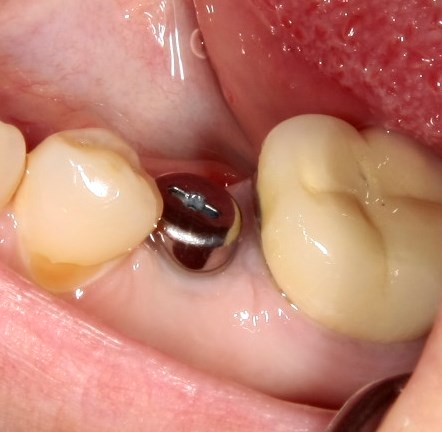

Немедленная имплантация — оптимальное решение в любой клинической ситуации